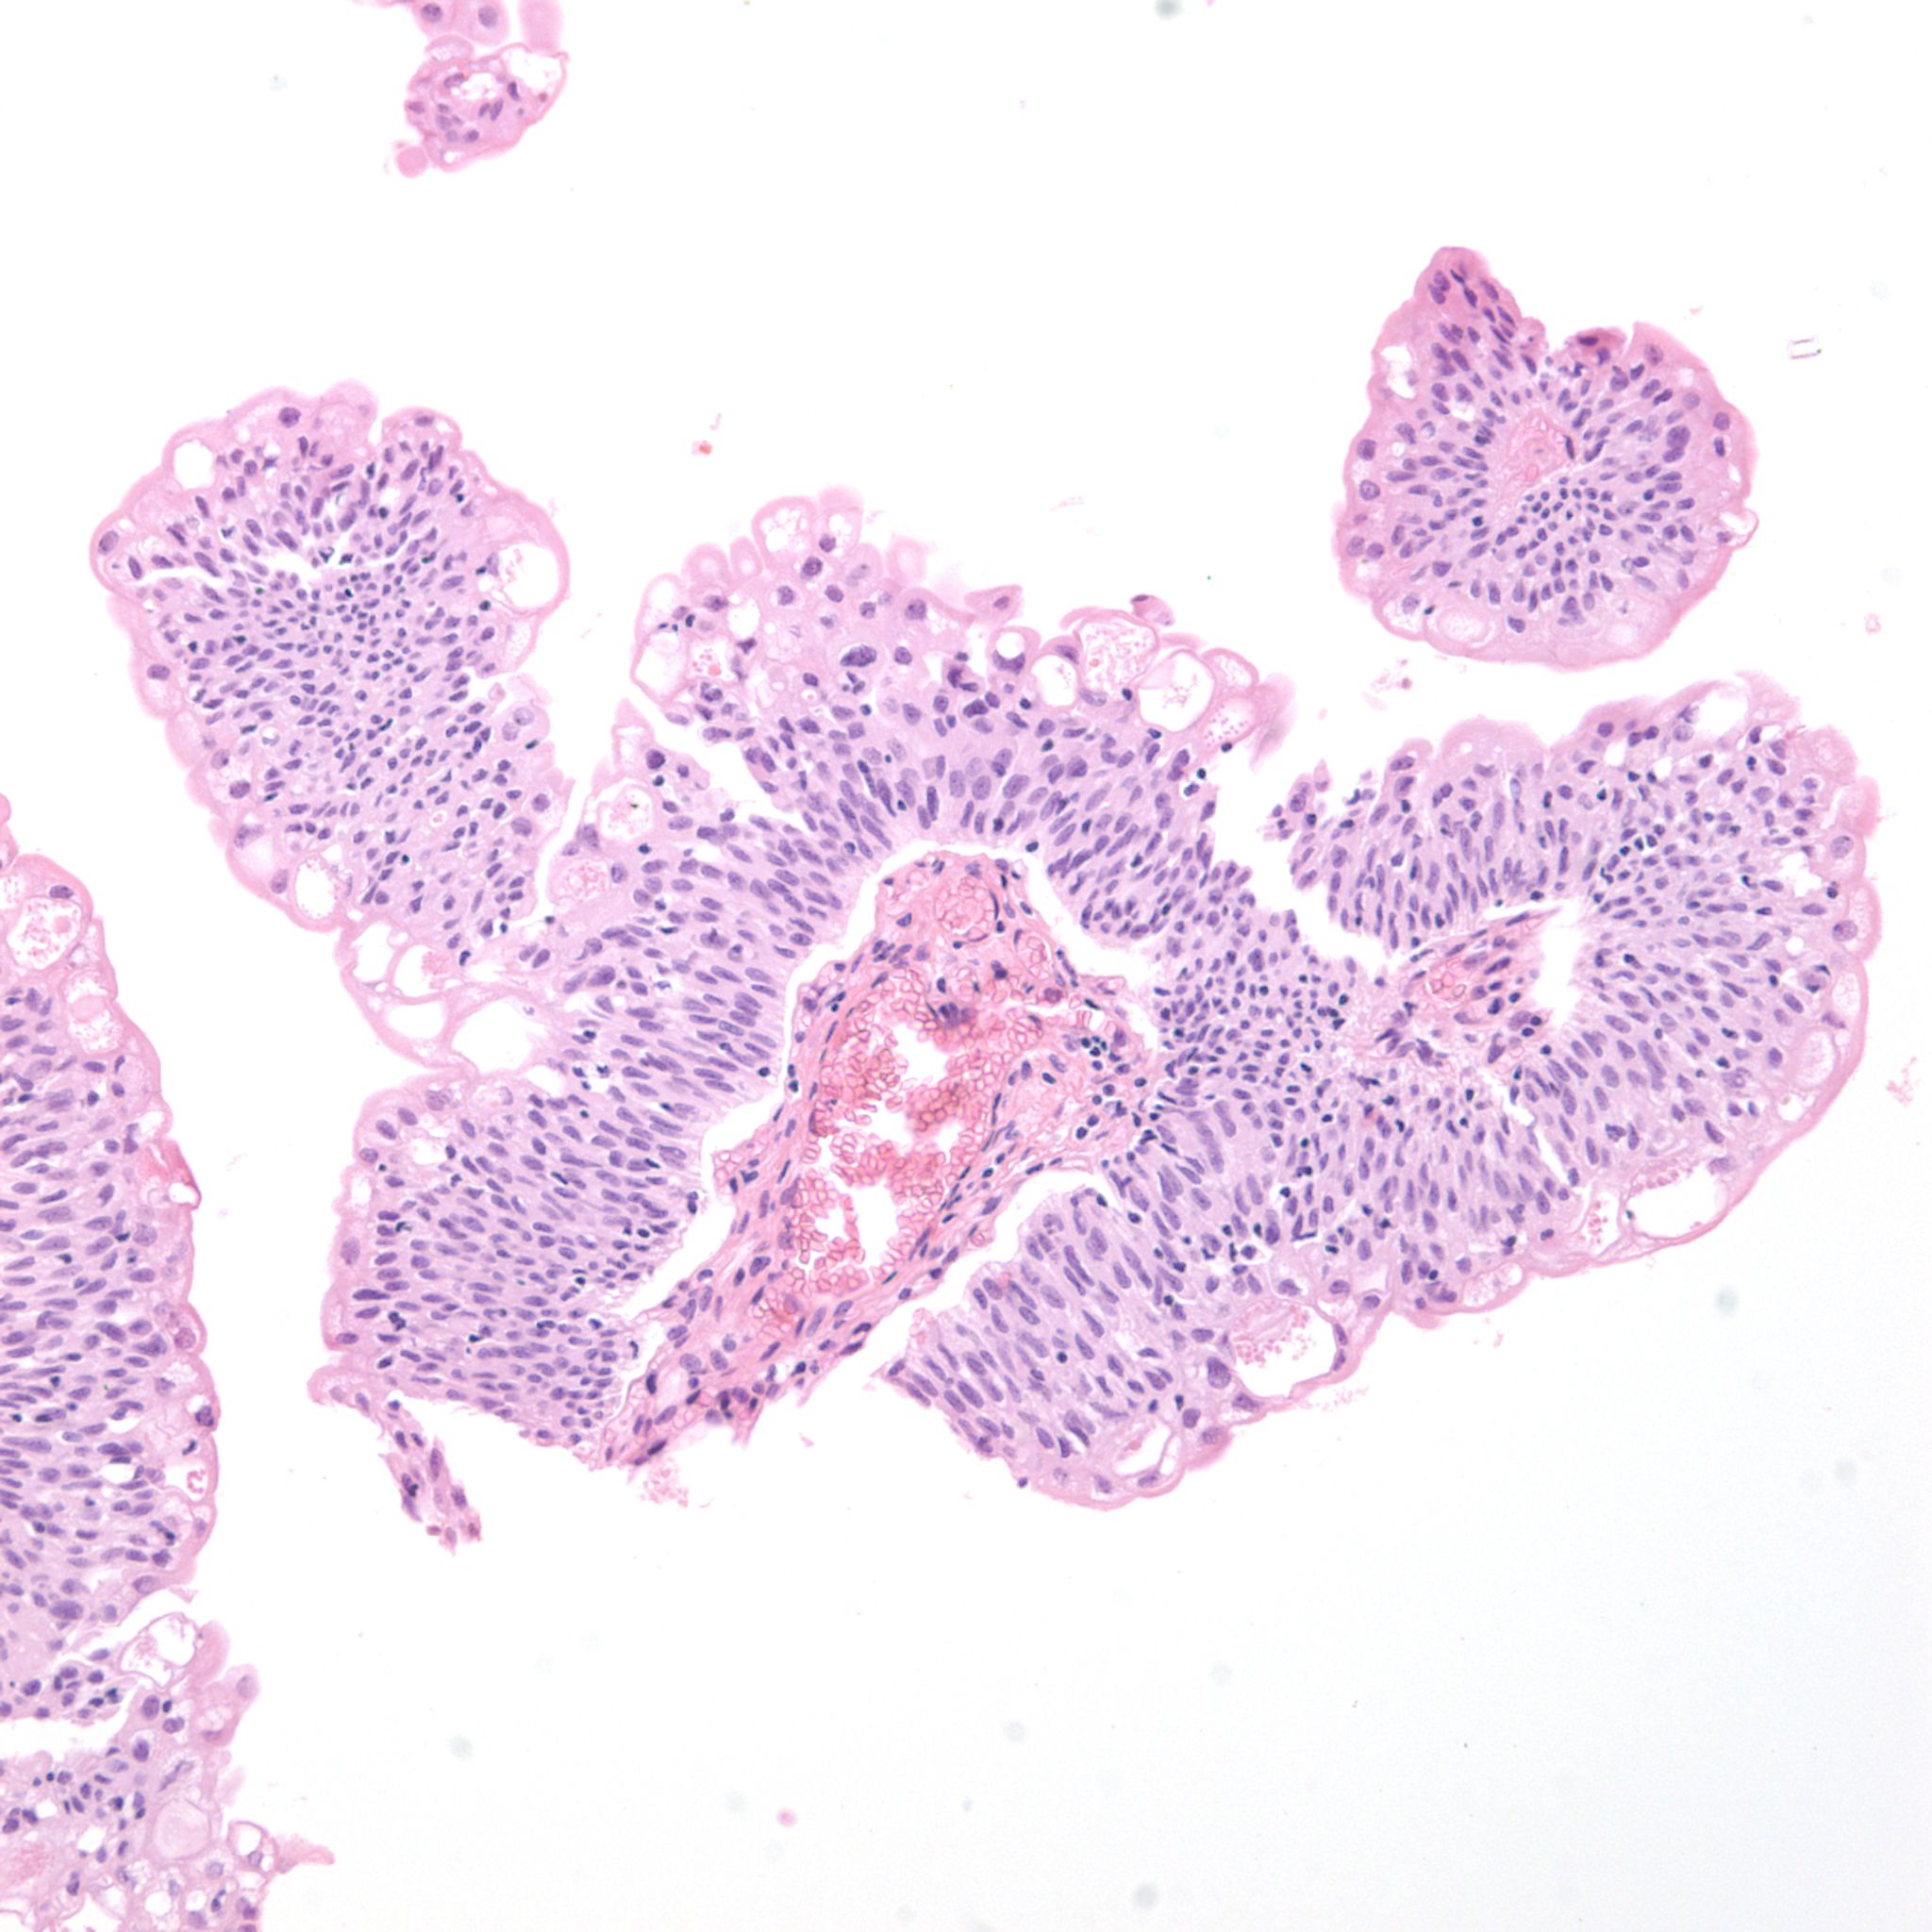

Bladder Papillary Lesions

Case ID: 303